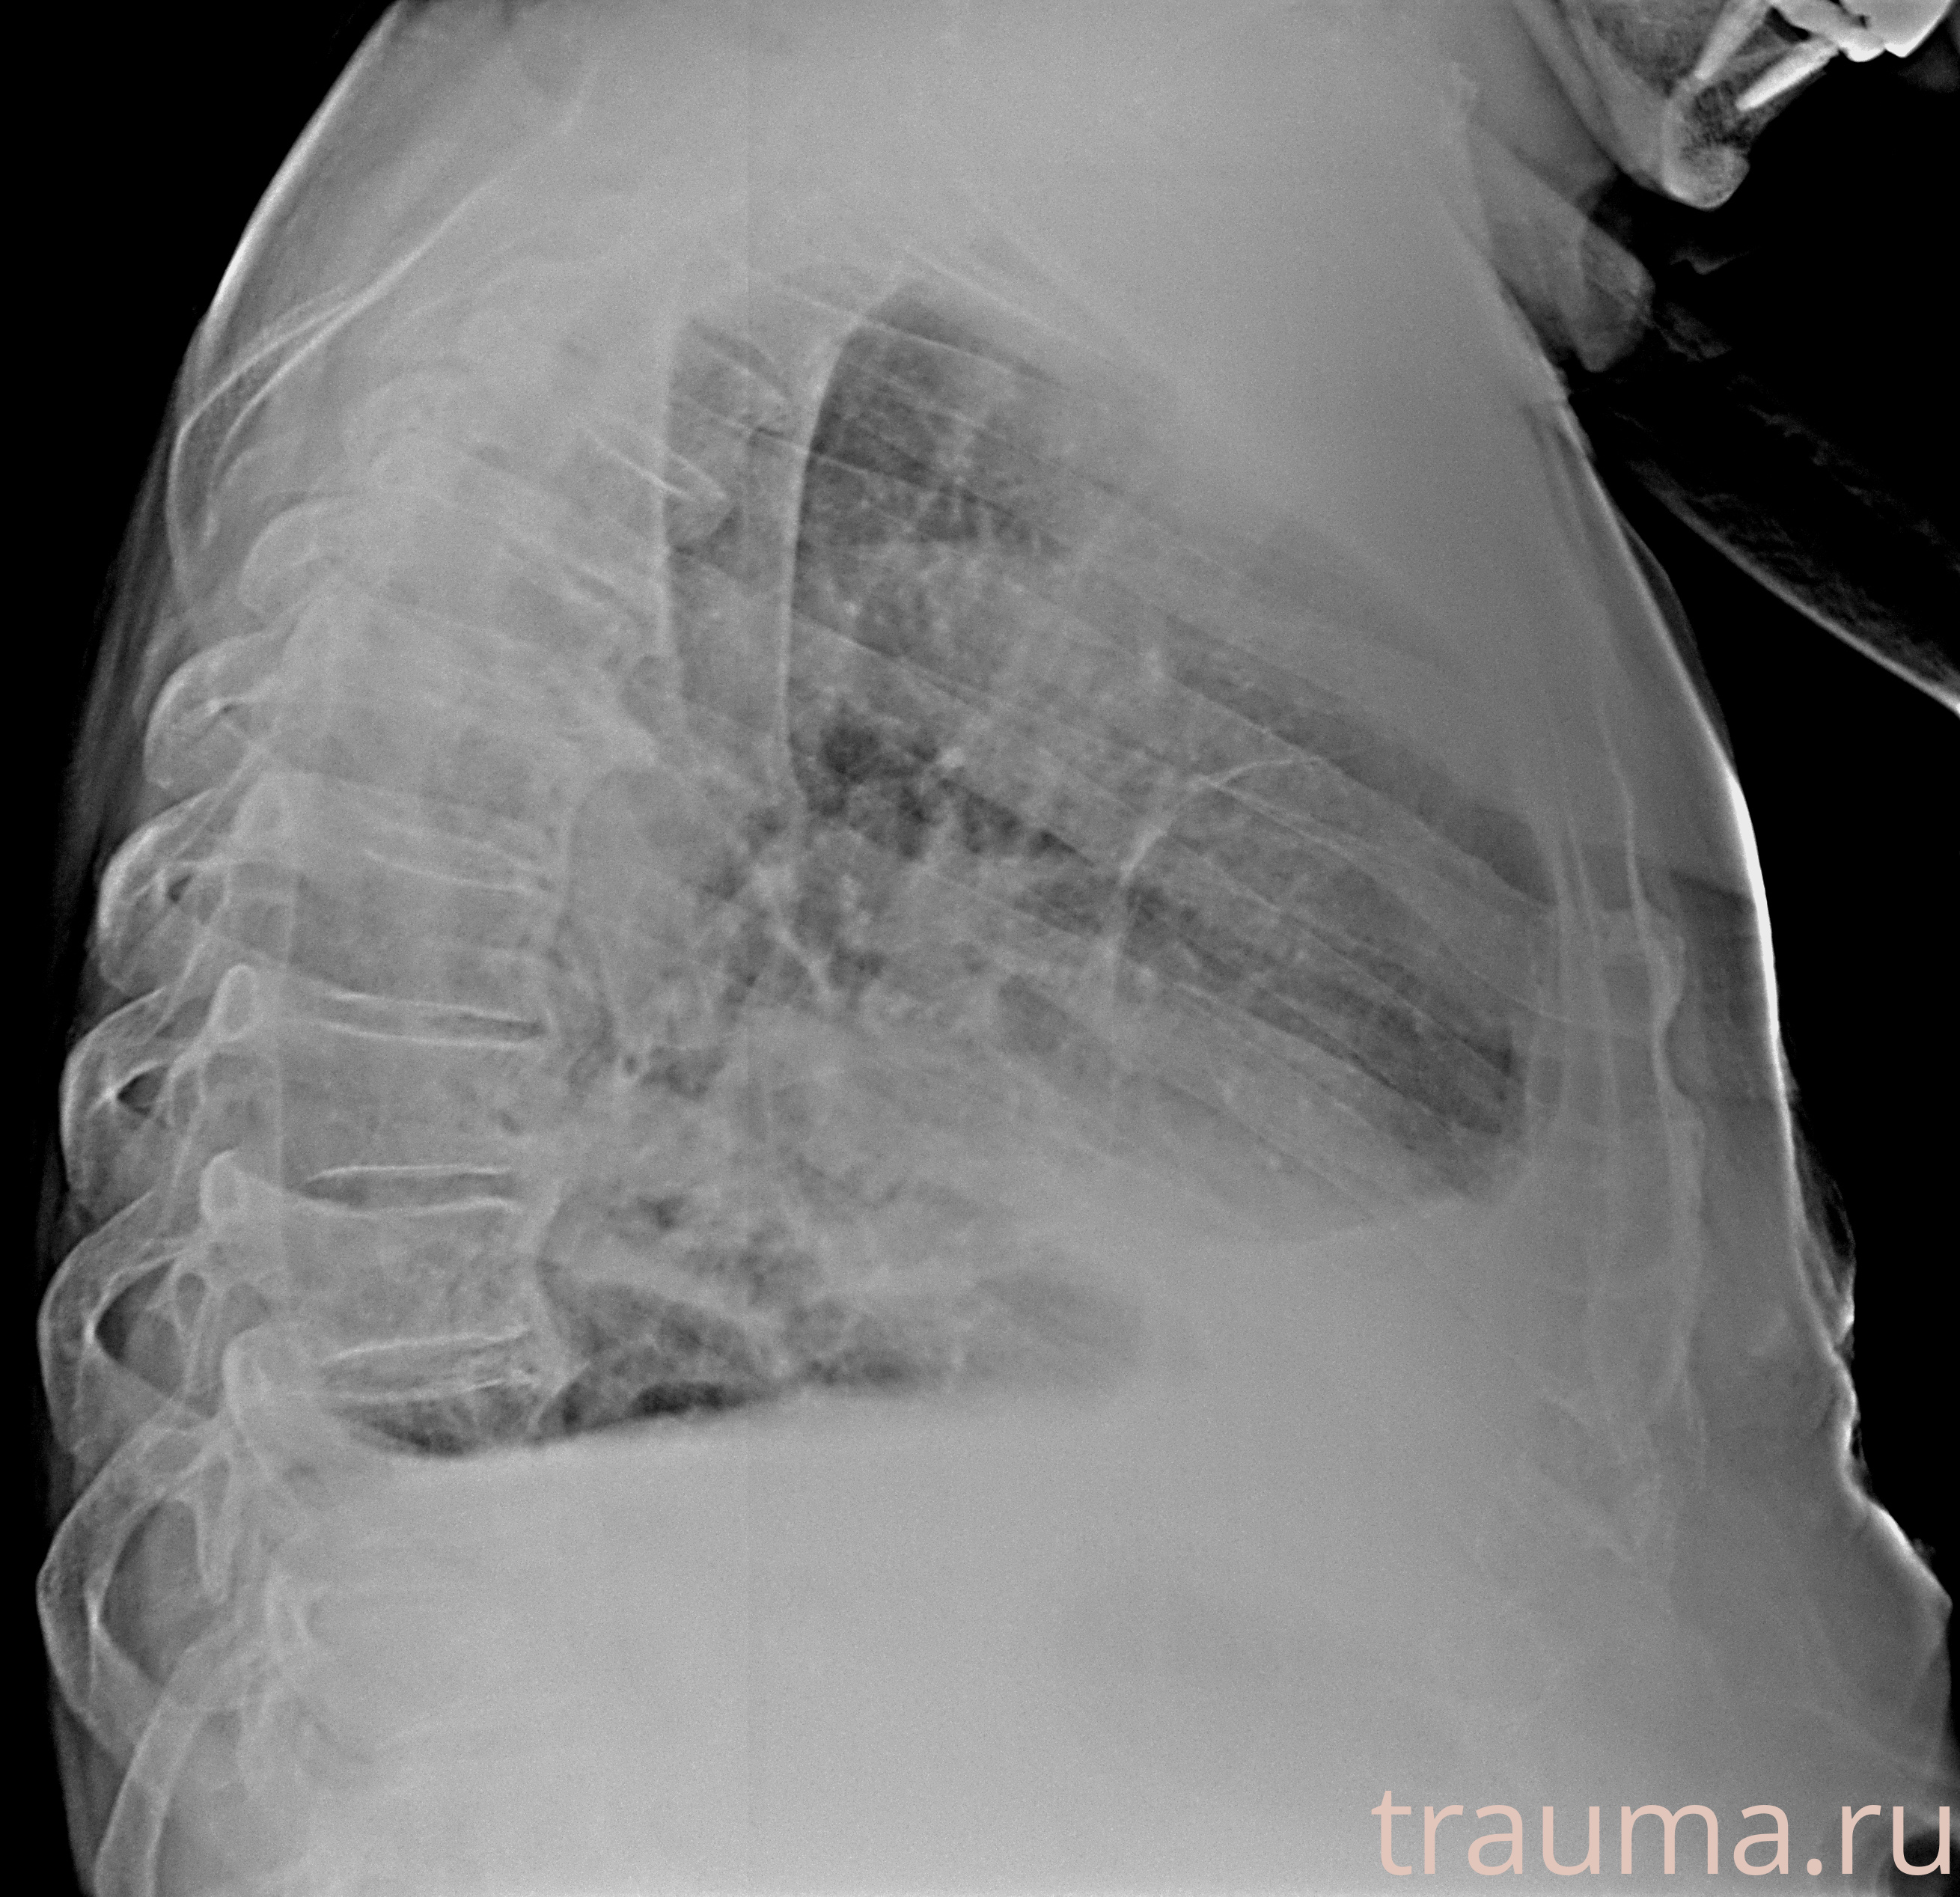

Рентгенограммы

Рентген на дому: по вашему адресу приезжает врач-рентгенолог, травматолог-ортопед с мобильным рентгеновским аппаратом, проводит диагностику травмы или заболевания, делает необходимые рентгенограммы, дает рекомендации по дальнейшему лечению. Получить качественные снимки в домашних условиях возможно благодаря уникальной методике, разработанной МосРентген Центром для института  Склифосовского

при переломе шейки бедра и пневмонии от компании МосРентген Центр - партнера Института имени Склифосовского